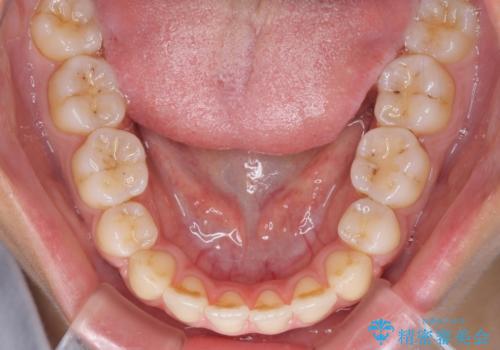

- 上の八重歯を気にして来院された患者様です。

受け口傾向にあるため、上顎前歯の叢生解消とともに下顎前歯を後方へ移動させることを目的とし、上下左右の第一小臼歯4歯を抜歯することとしました。

受け口傾向の方の下顎抜歯矯正では、下顎前歯の歯肉が退縮することがあります。前歯を移動させるときには、歯肉退縮が起こらないように工夫する必要があります。